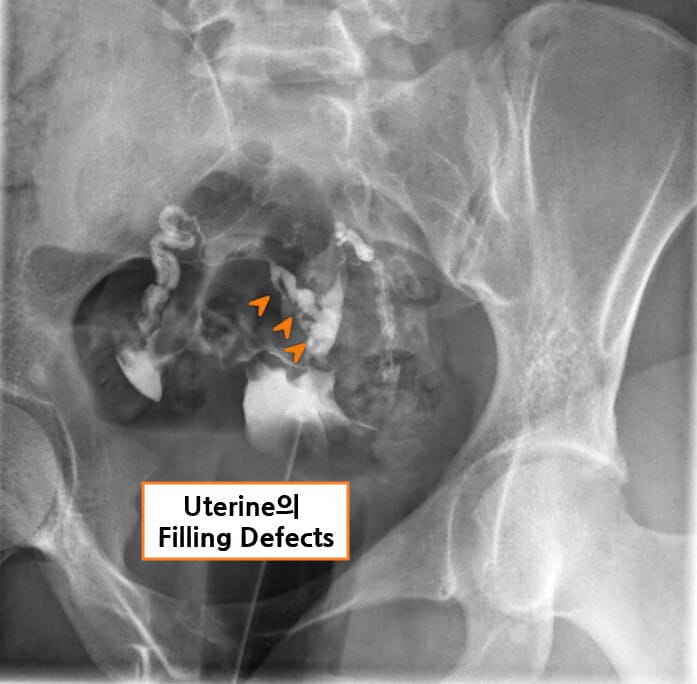

| 자궁난관조영술(HSG) |

| – 자궁강의 불규칙한 윤곽, 충만 결손(filling defect), 자궁강 일부 또는 전부의 소실이 관찰됩니다. |